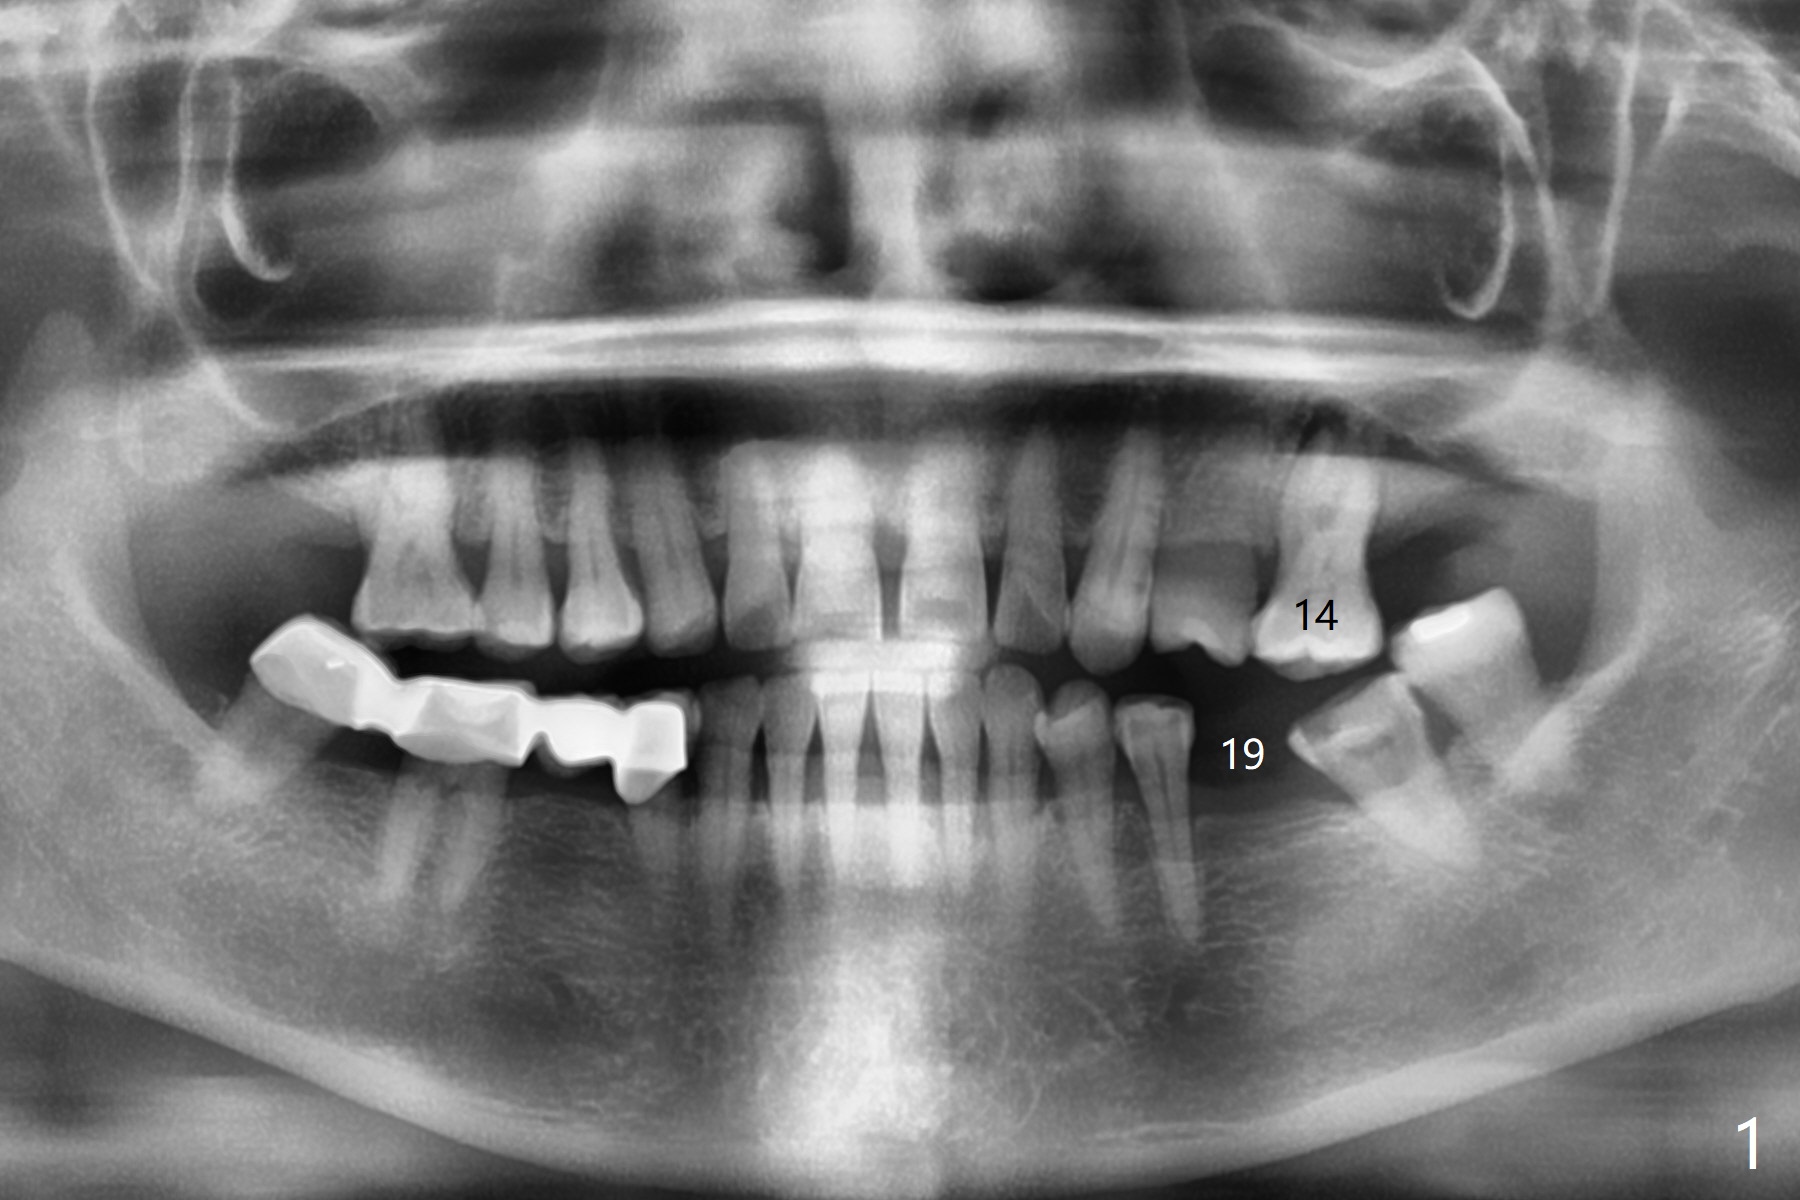

A 58-year-old woman with several restoration agrees to have implants at #15 and 19 (Fig.1). Since #18 tilts mesially, which needs to be trimmed, place #19 implant slightly distal, ~ .5 mm (Fig.2). As the infection at #14 is extensive (Fig.3), place #15 implant (probably 5x7.3 mm) distal, while tilts the long axis of the implant mesially (Fig.4 arrow). Also move the implant palatal with larger diameter and shortened length. Forget about the implant #15 if it is difficult or impossible to change.